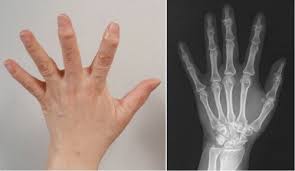

영상 검사

X선, MRI, 초음파 등 다양한 영상 검사를 통해 손가락 관절의 상태를 정확히 파악할 수 있습니다. 이러한 검사는 연골의 손상 정도와 염증의 위치를 확인하는 데 유용합니다.